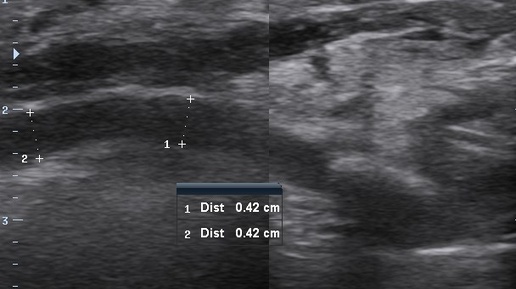

Конкремент в устье вартонова протока, сиалоаденит (УЗИ)